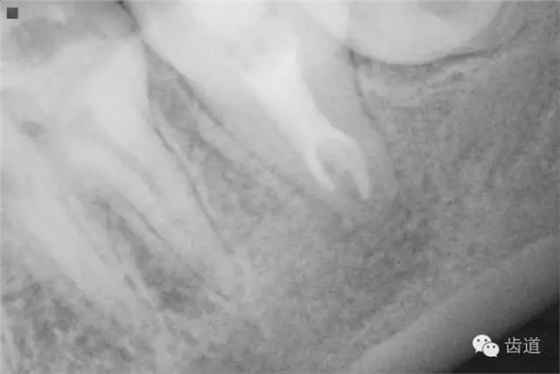

2. 術(shù)前X片

可見37根管影像清晰,根中上三分之二粗大,根尖三分一分為近遠(yuǎn)中兩根管,形態(tài)均呈弧形,根尖周膜連續(xù)性中斷,根尖周透射影明顯